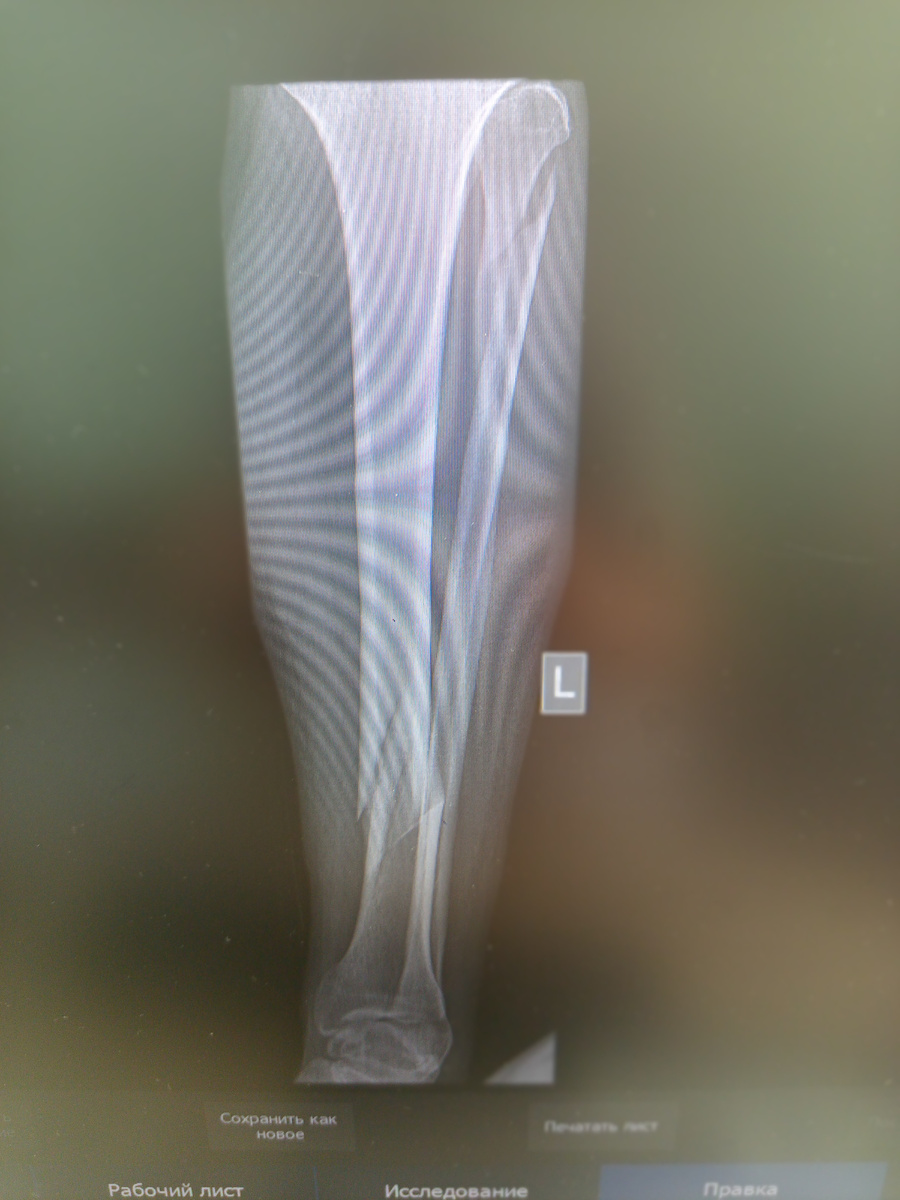

Завозит санитарка приемника каталку. На удивление , пациент раздет, проходит по отделению сочетанной травмы. Назначено снимать голову, легкие , таз и голень.

Подхожу к пациенту , и в нос шибает запах и немытого тела и перегара. Маска при этом не спасает.

Смотрю в базе , да , БОМЖ.

–Что случилось?

–С шестнадцатого этажа упал!

–С какого!?

–Да шучу я , метров с полутора.

–Почему упал?

–На салют вчера засмотрелся!

–Ну, и как салют?

–Зашибись(не то слово )! Понравился.

Ночь бомж Сергей промучился , а утром вызвал скорую(не удивляйтесь, у него есть мобильник, да , простенький, но есть).

-2

Сломал знатно. Теперь будет обеспечен кровом и едой, как минимум на полгода. Его не выпишут после операции, некуда.А там смотреть уже будут , как по состоянию.